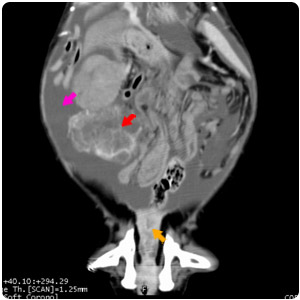

| 腹腔腫塊(紅)、腹水(黃) |

腹水(紫)、腹部腫塊(紅)、子宮殘段(黃) |